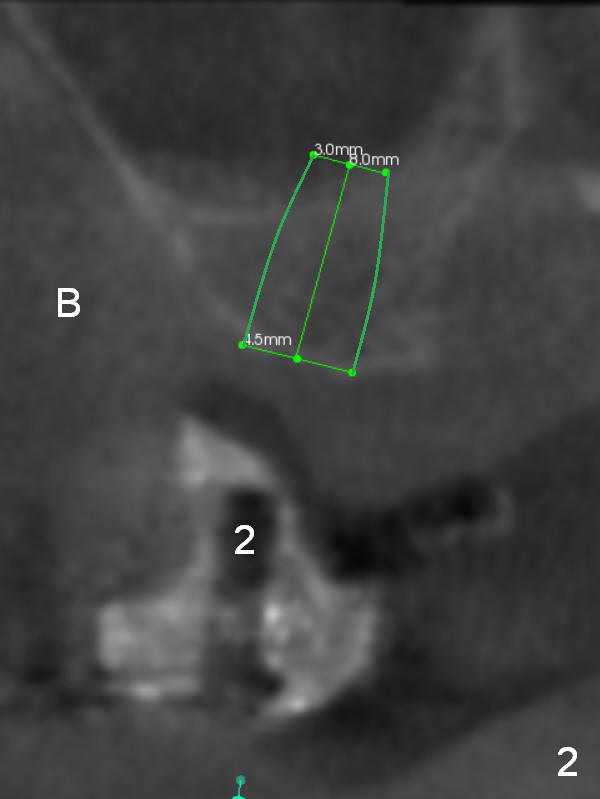

As mentioned earlier, the 56-year-old man is taking Plavix, one tablet every other day. The last time he took the medication is 4 days ago. For hemostasis, three carpules of 2% Xylocaine with 1:50,000 Epinephrine are administered in infiltration. Initial osteotomies are established through the CT scan stent (Fig.1-4: #2-4). Then an incision is made. After raising the flap, the osteotomy sites are checked. Ridge split is made between these sites with a chisel without much success. Bone is soft between #2 and 3. Sinus lift (Fig.2,4) is attempted at #2 and 4 (3.6 mm), whereas bone expansion is accomplished at #3, in the bone between the sinus (Fig.3 S) and the nasal cavity (N).